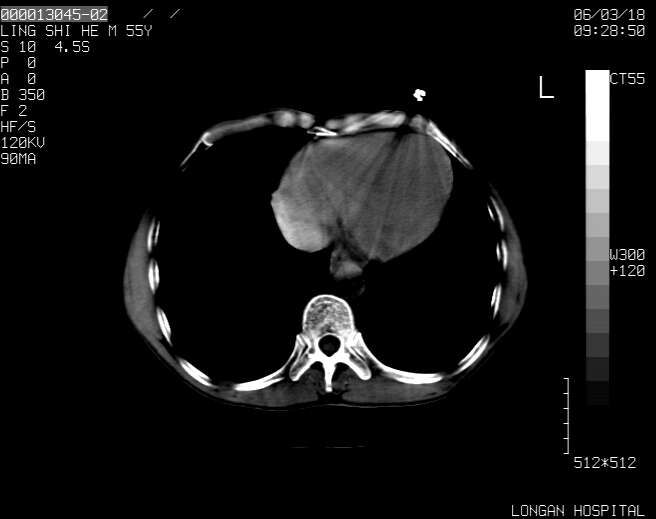

以下是引用guzhongliangddd在2006-3-21 22:13:00的发言:[br]病灶主要位于肝右叶的后份,内见异常血管,门脉主干及右支受侵{提示有癌栓形成},门腔间隙内见增大淋巴结。肝左叶内未见异常。

以下是引用zhuxinli在2006-3-22 1:23:00的发言:[br][br] 病灶主要位于肝右叶的后份,内见异常血管 .门脉右支截断,右叶前段早期强化(考虑动静脉漏),腹膜后肿大淋巴结,病灶逐渐强化,考虑为胆管细胞癌[br]